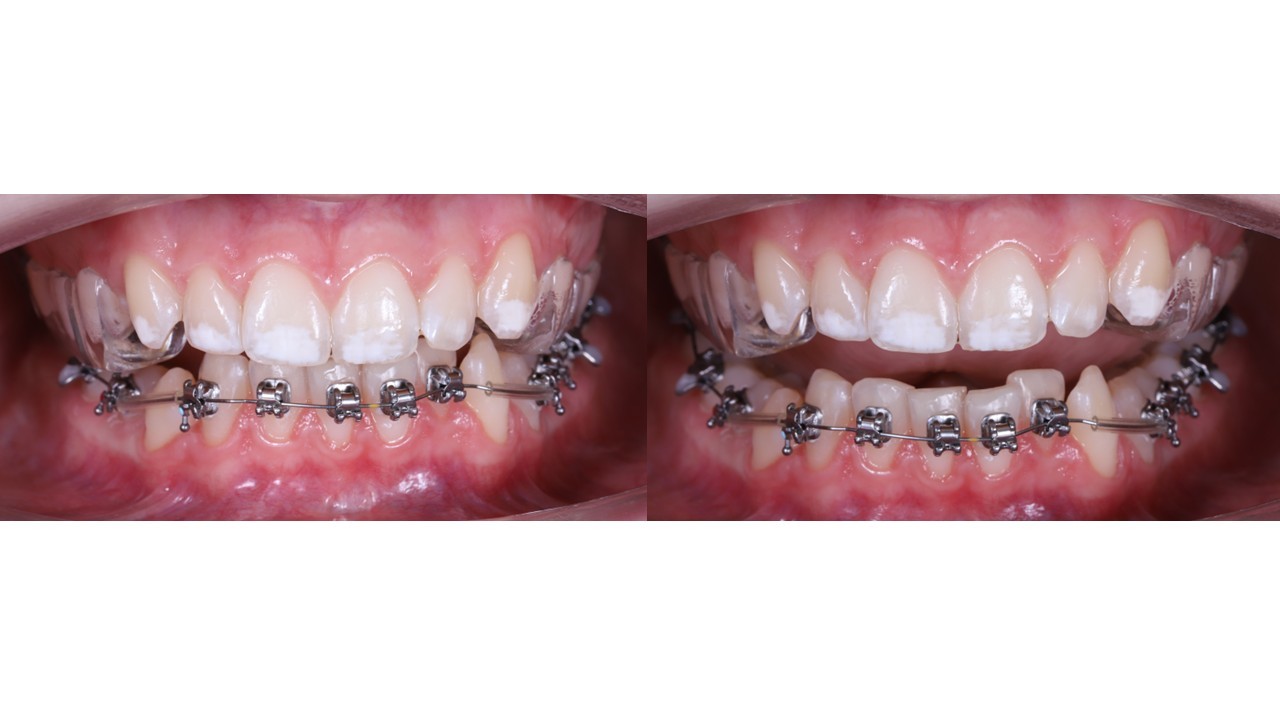

Як закрити відкритий прикус інтрузією бічних зубів

Все про закриття відкритого прикусу з контролем вертикального компоненту ISC-імплантами і плануванням по VTO. Без інтрузії навмання

→ Задаєш вертикаль ще на плануванні ортодонтичного лікування